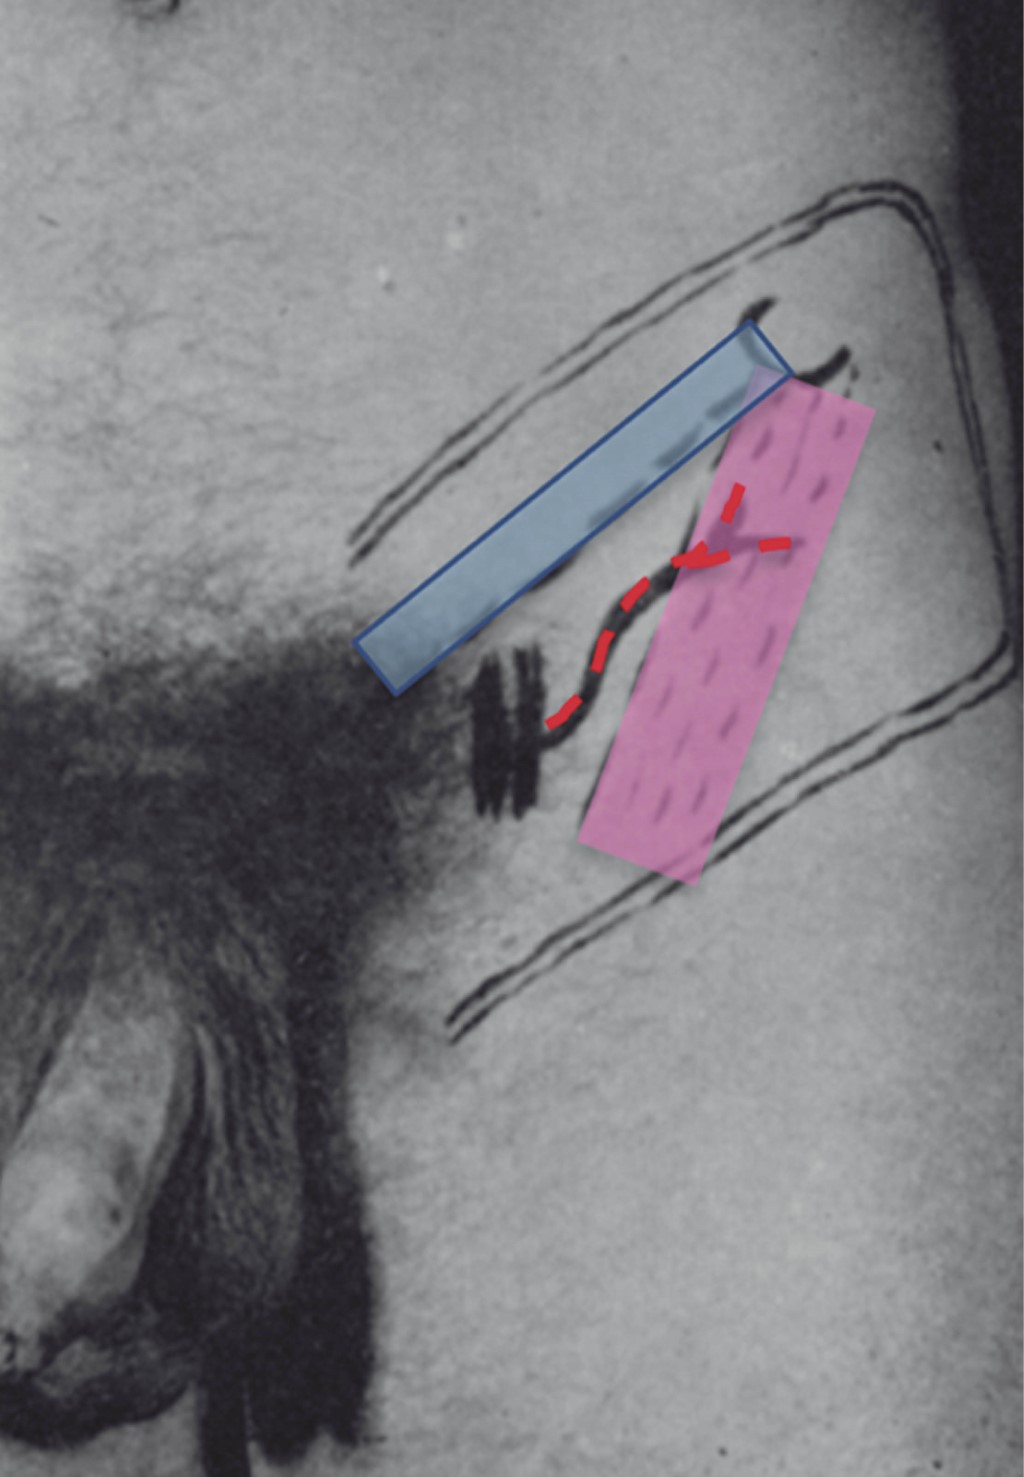

La técnica quirúrgica se realizó con la paciente en decúbito supino, posicionando un cojín bajo la región glútea derecha para facilitar el abordaje. Se efectuó el marcaje quirúrgico delimitando el área de diseño del colgajo, tomando como referencias anatómicas la espina iliaca anterosuperior, la espina del pubis, el arco crural y el músculo sartorio (Figura 1). El extremo distal del colgajo se modeló para adaptarse a la forma y dimensiones del defecto, manteniendo siempre al pedículo vascular centrado.

Figura 1